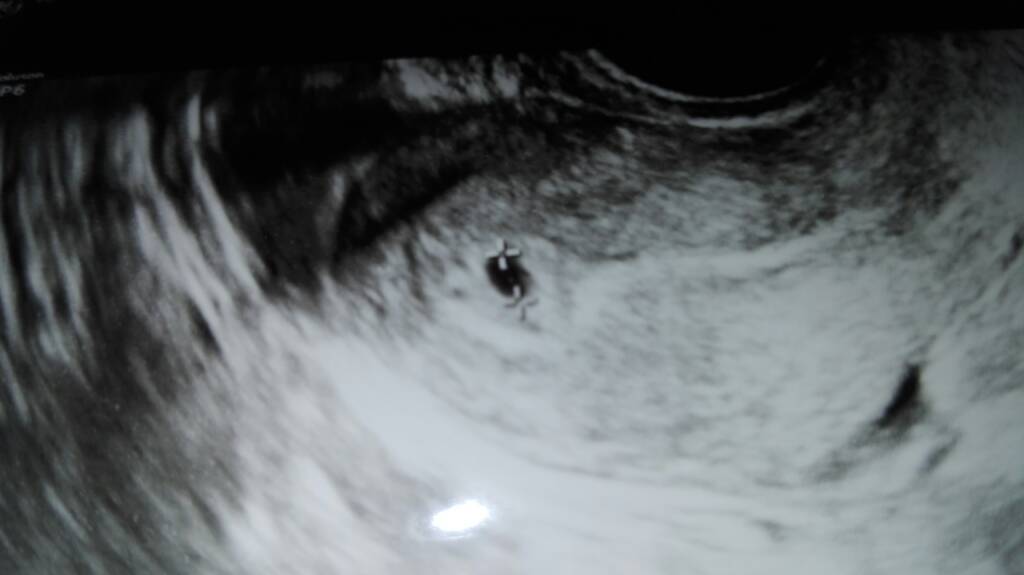

Przedstawiam.wam mojego orzeszka.

Ma 4 mm i jest ladnie.iejscowiony.

Drugiego lekarz nie znalazl, ale tez jakos nie szukal mocno.